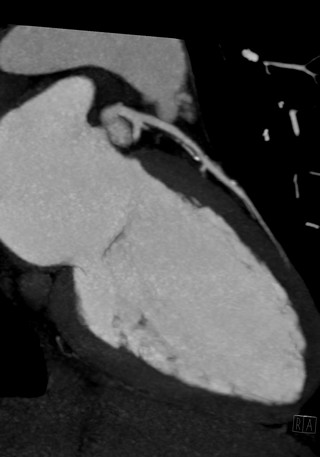

Artère interventriculaire gauche et artère coronaire droite